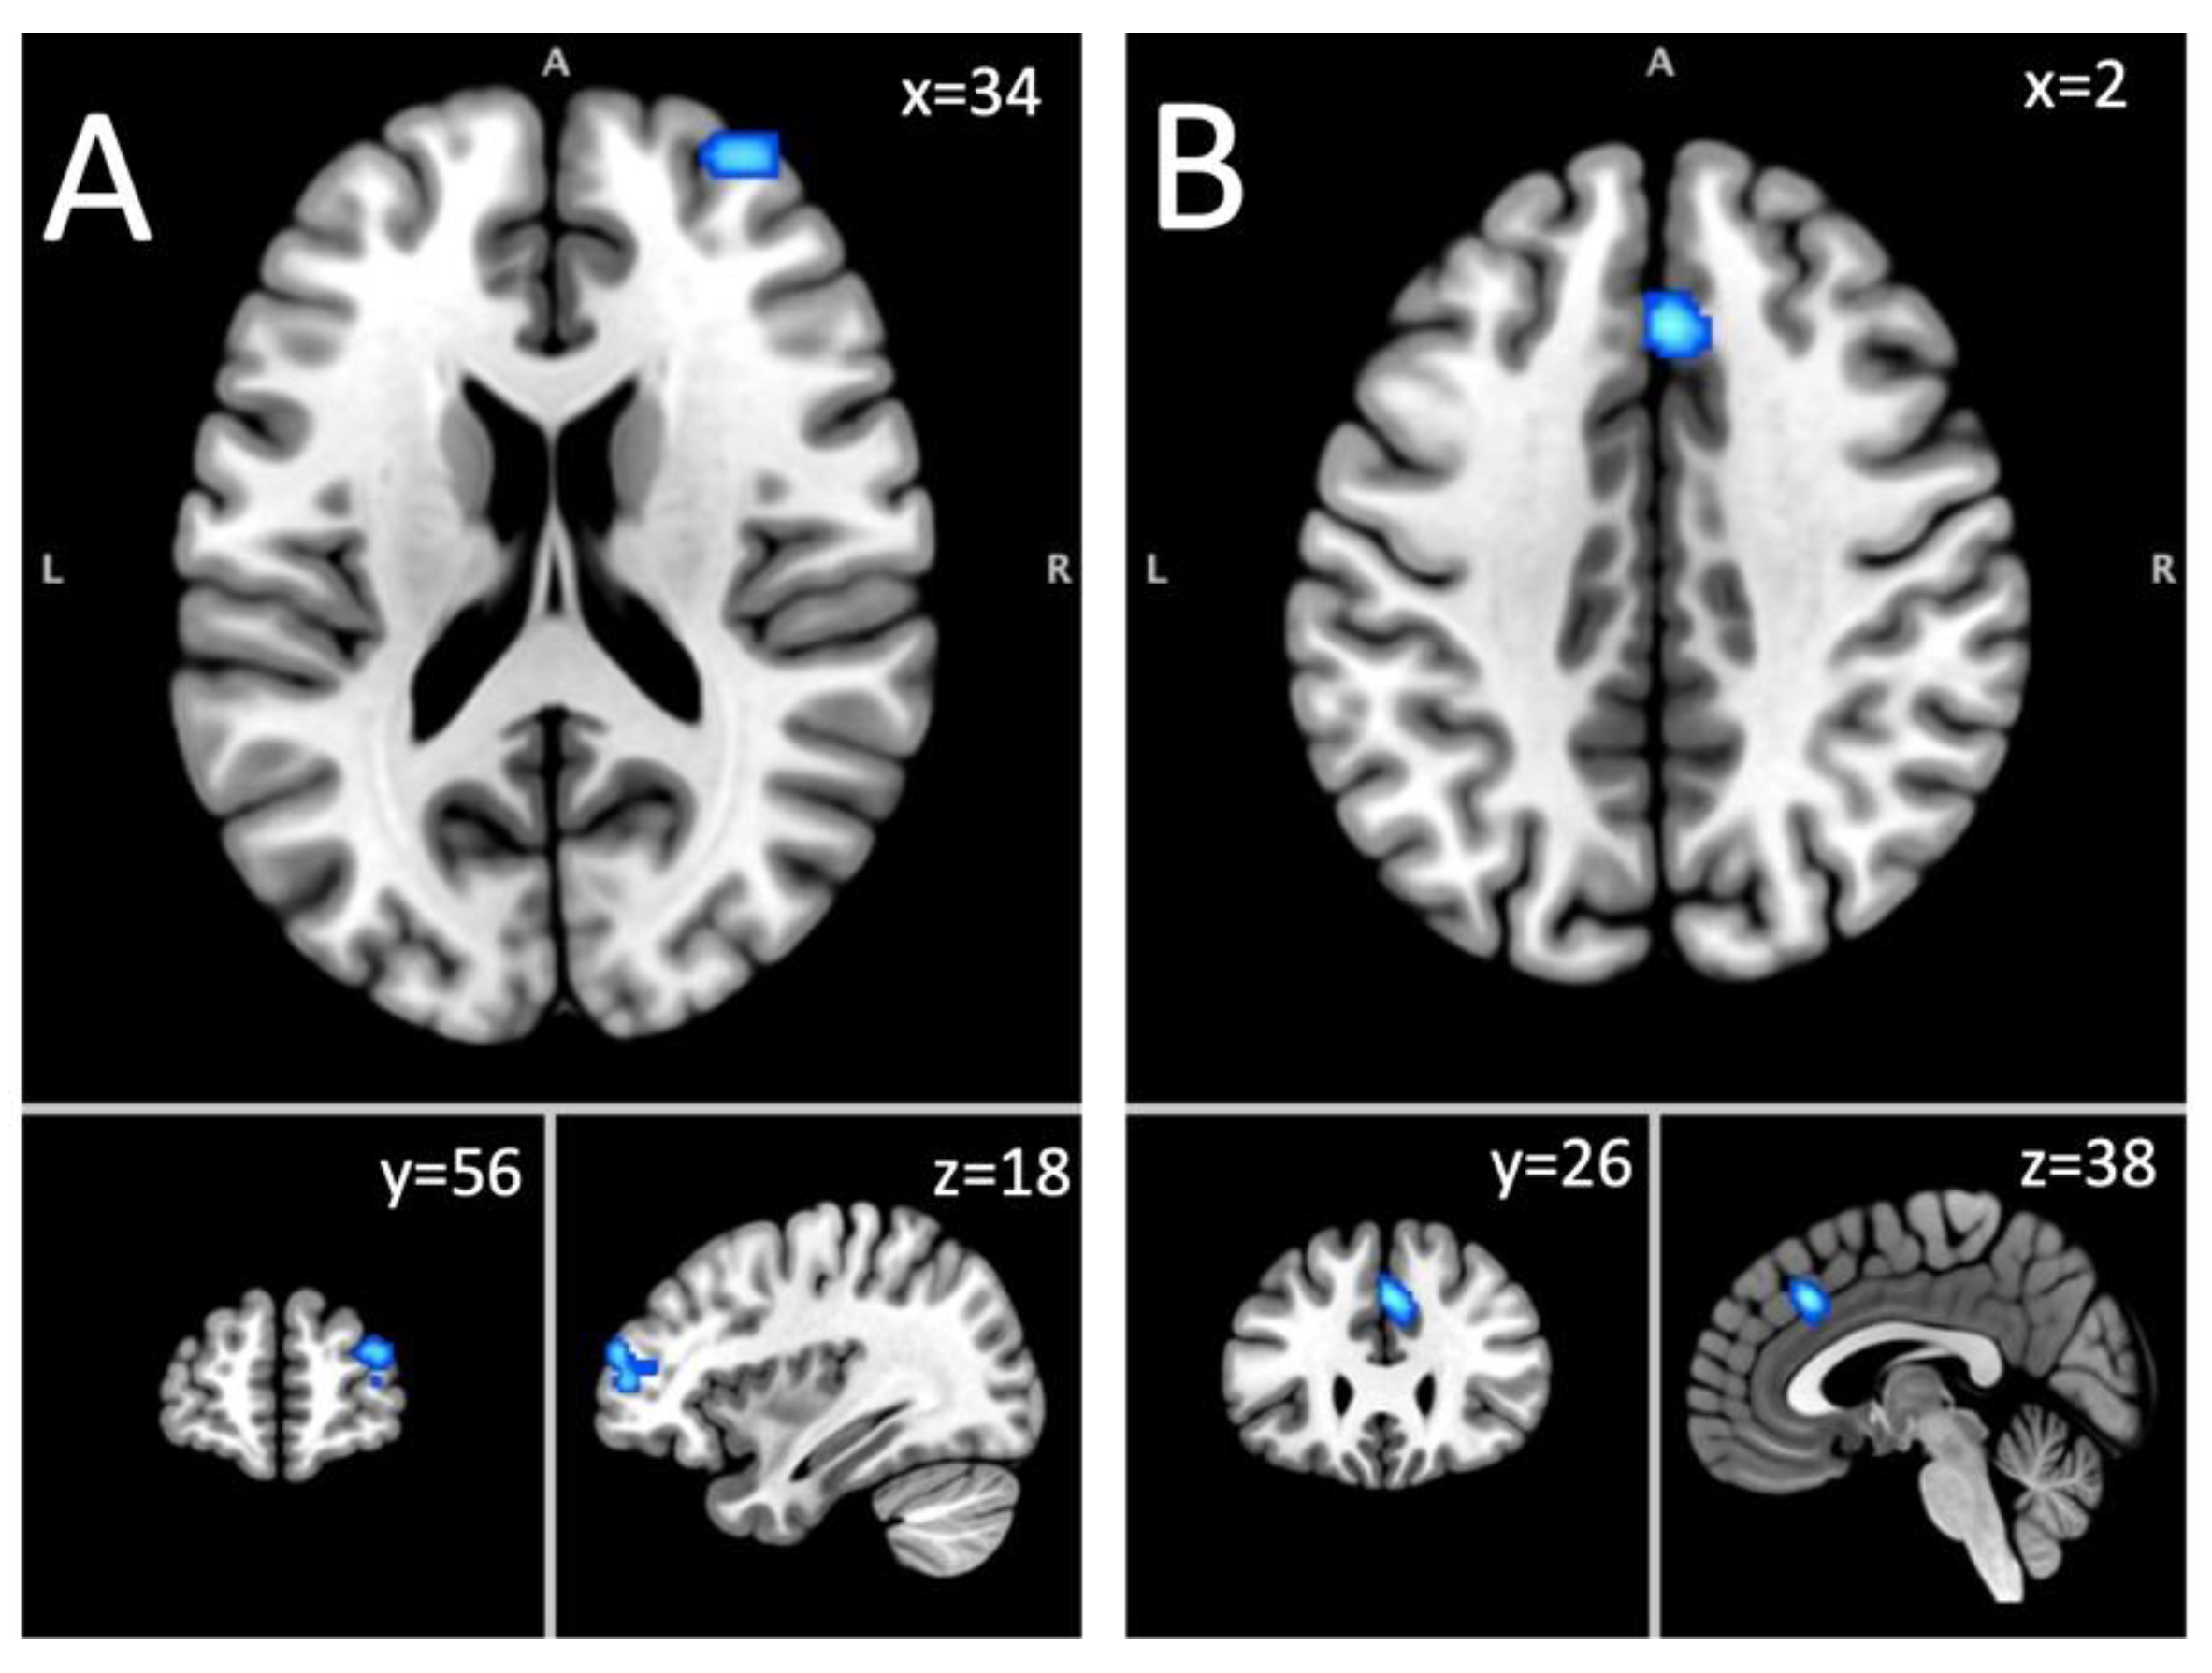

| Superior frontal gyrus, middle frontal gyrus | R | 856 | 0.0147 | 3.85 | 34,56,18 |

| Cingulate gyrus, medial frontal gyrus | R & L | 800 | 0.017 | 4.26 | 2,26,38 |